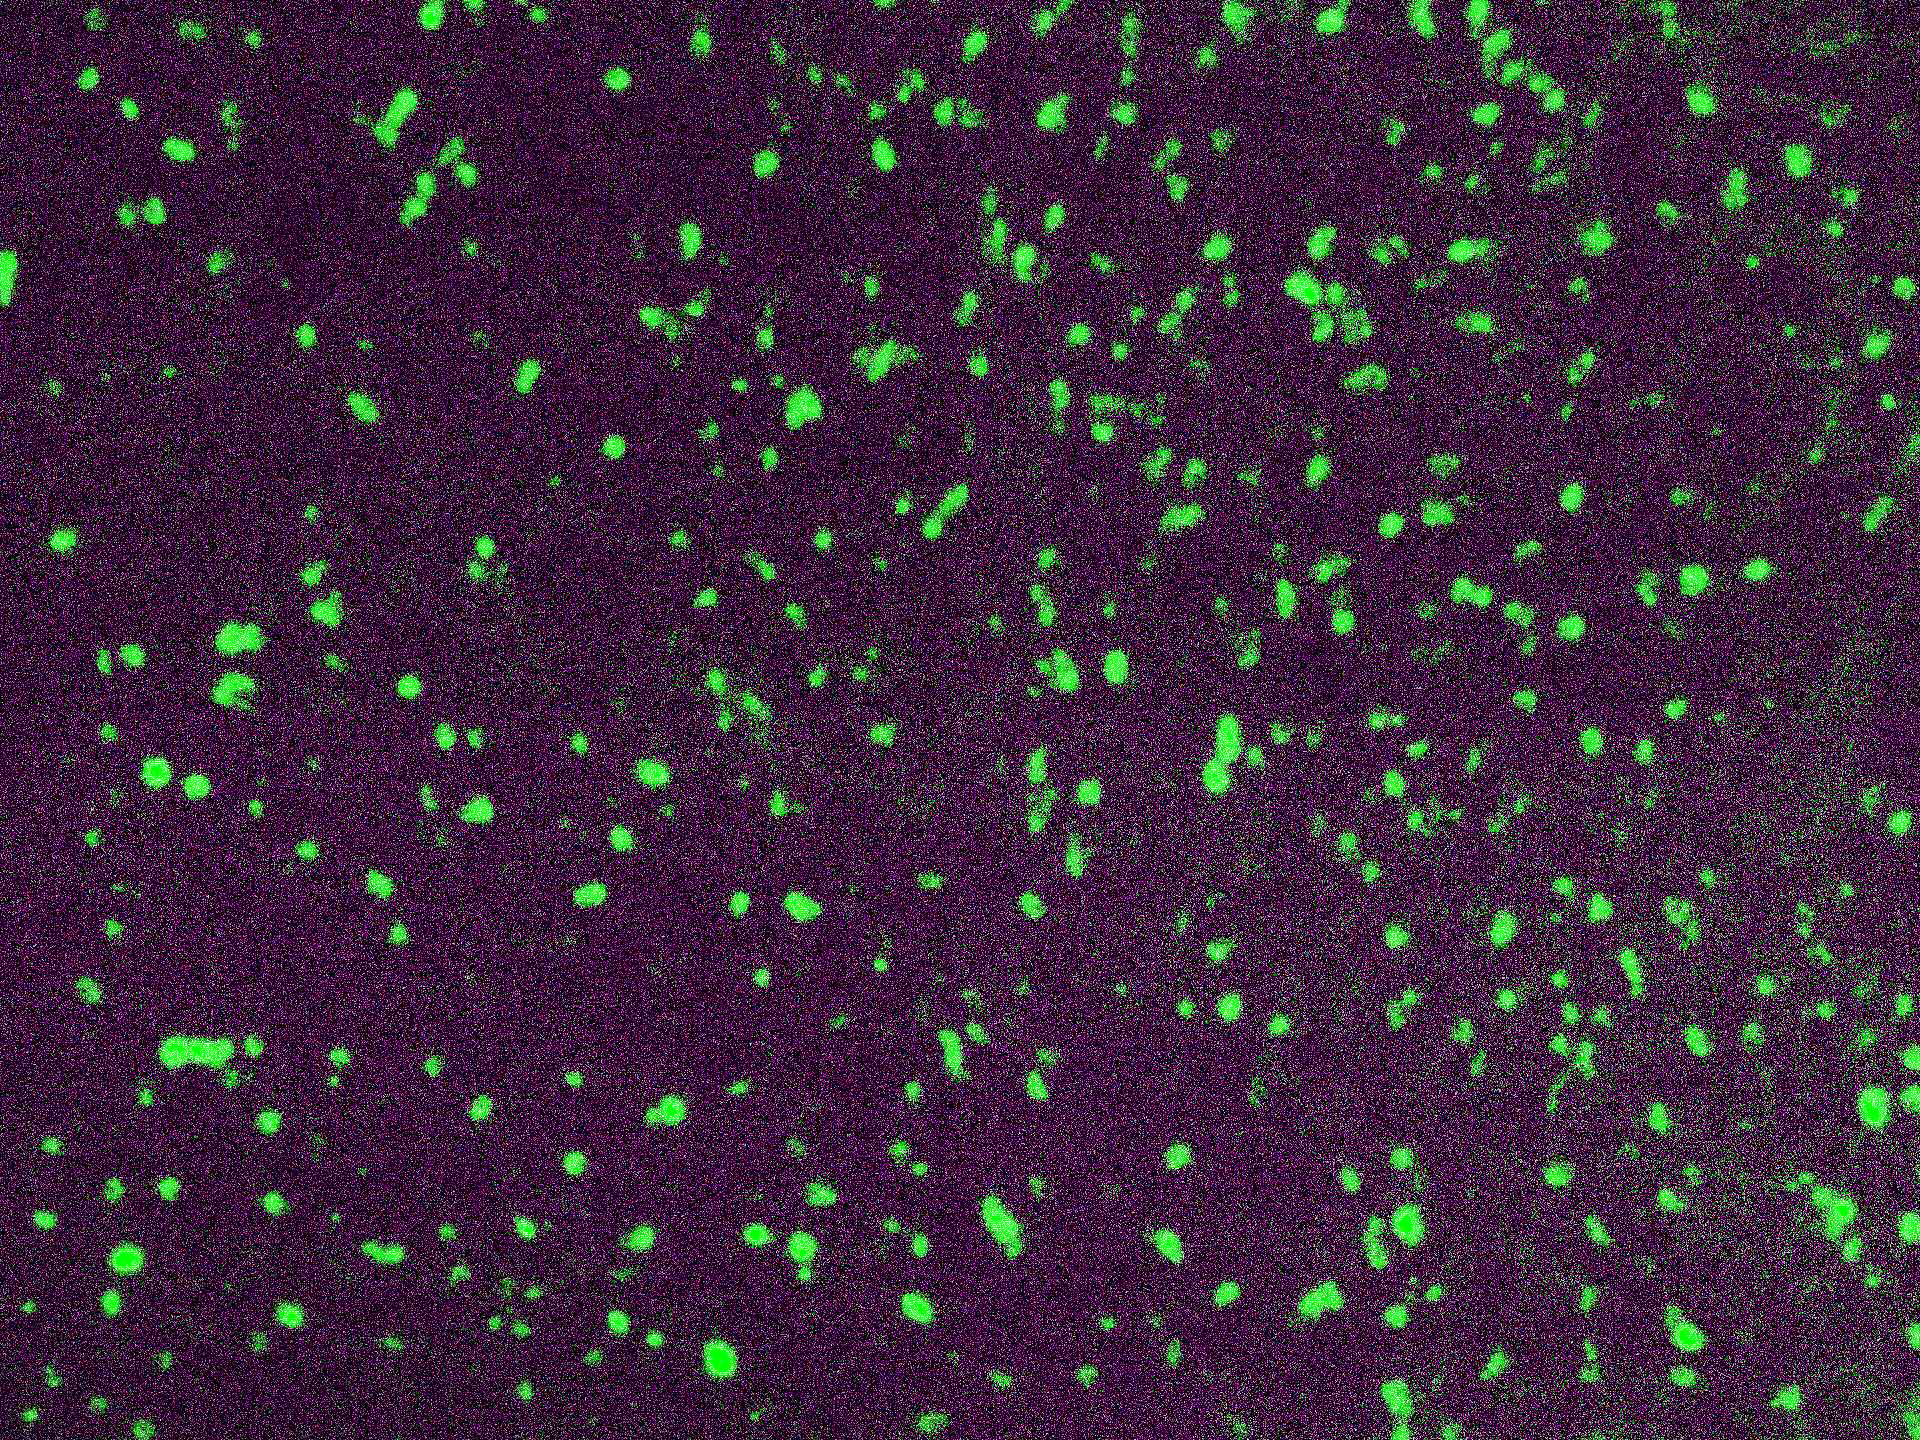

Lambda Light Chain-FITC

Traces of contaminating antibodies have been removed by solid phase absorption. Only the lambda precipitation line appeared in cross immunoelectrophoresis. This antibody is well suited for tissue section staining but may also be used for other applications.

| Description/Type | FITC Conjugated Antibody |